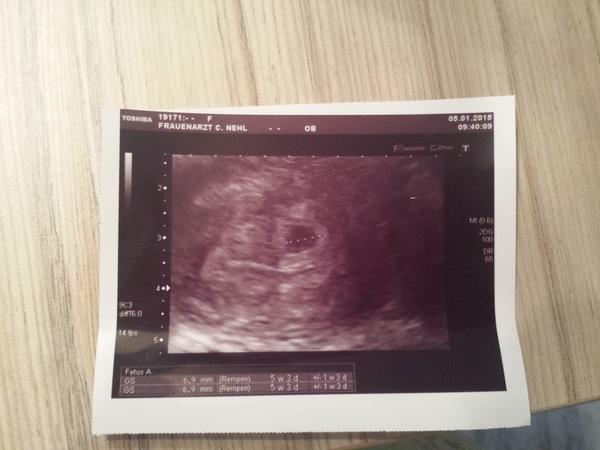

@ivankaberrynka ahoj neplatila som nic ale ja som v Nemecku čiže neviem ako je to na SK. Držím palce aby bolo vsetko ok. 😉

@all, dnes som bola prvýkrát u doktorka, tehotenstvo potvrdené, bábätko je tam, kde má byť, srdiečko bilo, také malé vynikajúce 🙂 tak už len nech pekne rastie, kontrola o dva týždne 🙂

ahoj babenky,takze dnes som mala kontrolu u svojej lekarky. Mala by som dnesnym dnom byt 5t+5 a urobila mi sono a zistila ze gastracny vak je krasny a aj s malou bodkou ktora je zltkovym vakom a presne zodpoveda asi 5 tyzdnu. Dobceka este vidno nebolo vraj to je este velmi skoro ale ze vsetko je na najlepsej ceste ako ma byt.Tak som sa trosku ukludnila i ked som s usmevom na tvary odtialneodisla kedye som dostalainjekcie Fraxiparin a este dalsie injekcie a aj nejake tabletky teda hormoniky,vraj kedze som uz mala 2 krat MA ze uz to teraz nechce riskovat a musi ma ochranit z kazdej strany. Vraj to je len docastne na najblizsie 2 tyzdne a potom sa rozhodne ci mi uz len ostane fraxiparin najnizsia davka pre istotu.Tak uz som dnes hned dostala dve injekcie a teray hura kazdy den dalsie juj to bude zabava ale kvoli malemu drobcekovi asi dokazeme vsetko. Najblizsia kontrola bude za 10 dni vraj to uz uvidime kompletne vsetko tak sa snazim byt optimista a tesit sa a verit ze vsetko bude dobre.